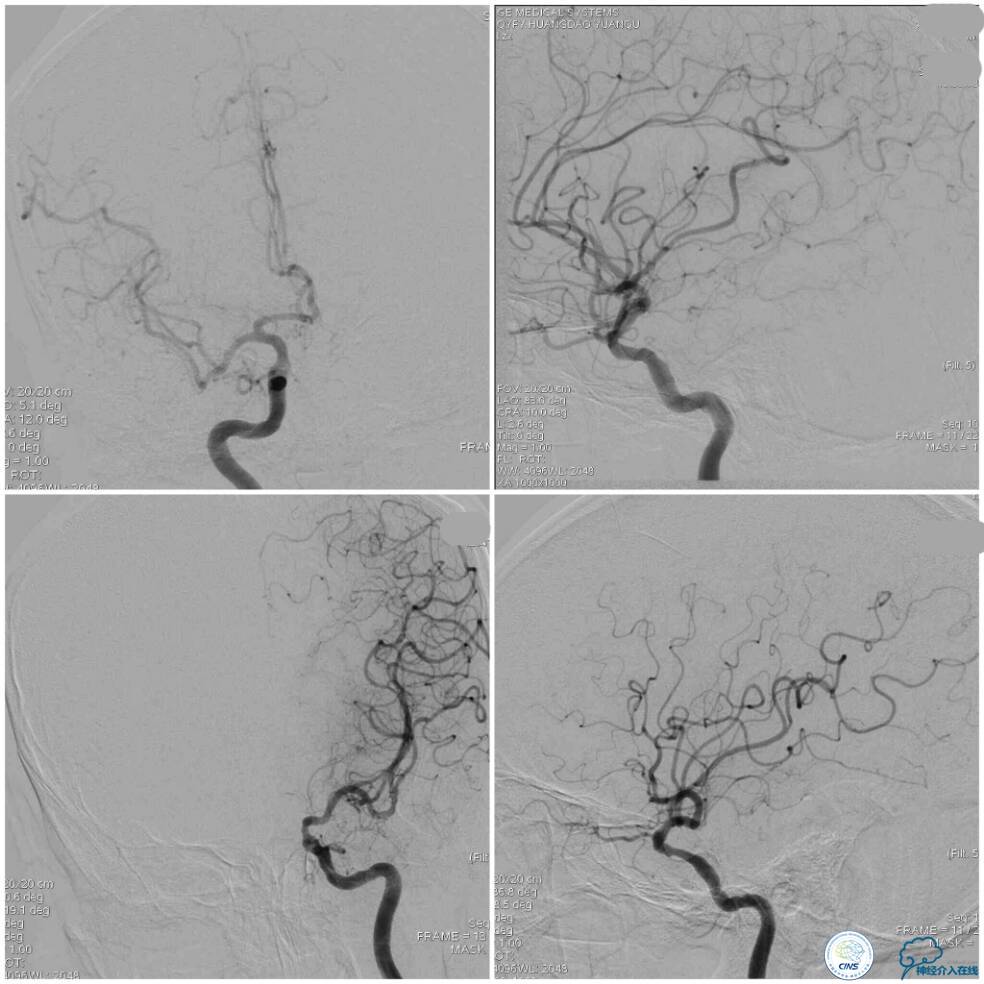

全麻下双股动脉穿刺,分别置入6F及5F动脉鞘。6F导引导管置于右椎动脉V2段,Traxcess 微导丝与Echelon 10微导管同轴,经多次尝试后送达基底动脉(图8);操作过程中见微导丝头端打折变向,此时手控导丝有阻力感,考虑是闭塞病变的近心端(图8箭头),当微导丝越过闭塞段进入血栓,此时微导丝及微管前行无明显阻力。

微导管造影证实在基底动脉真腔后,交换技术送入Transend微导丝(0.014″300 cm)至左侧大脑后动脉P1段,送入Gateway球囊(2.0 mm×9.0 mm)从闭塞段远端向近心端扩张4次,扩张完造影示右椎动脉V4段无再通(图9)。

此时经6F导引导管和放置在左椎动脉V1段的5F椎动脉造影导管行双路径图,以显示椎基底动脉系统。选用Apollo球囊扩张支架(2.5 mm×13 mm 3枚,3.0×8 mm 1枚)自闭塞远端至近端依次释放支架,两个支架间重叠约2 mm(图10)。

支架释放过程中给予替罗非班3 ml/h静脉持续泵入,以预防急性血栓形成。最后一枚支架释放完毕后造影显示右椎动脉V4段再通,支架贴壁良好,前向血流TICI分级3级,左椎动脉V4段逆向显影(箭头)(图11)。